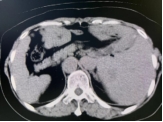

术前影像

60岁的胡女士因结肠癌于2023年1月接受了肝左外叶切除+右半结肠切除+肝右叶肿瘤切除手术,2023年12月复查时发现肝脏出现新的占位,考虑为术后肝内多发转移,一处病灶靠近心脏位置,另外一处病灶靠近肾脏,如若再次手术,不仅创伤大,而且对术后病人的康复不利,胡女士慕名来到我院介入科,团队通过仔细评估并组织讨论,与胡女士及家属充分沟通,决定采用“复合式冷热消融术”创新治疗方法。